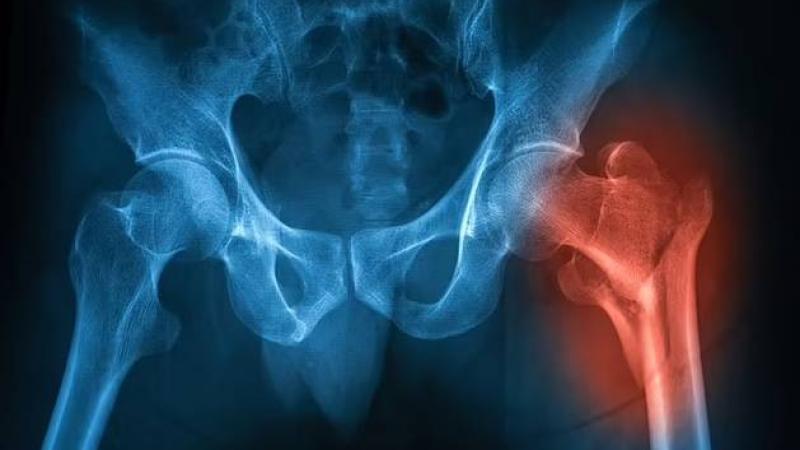

أشارت دراسة أجراها باحثون صينيون في جامعة سنترال ساوث، بتشانغا، إلى أن العيش في مناطق خضراء، يزيد من كثافة العظام، وانخفاض خطر الإصابة بالهشاشة، وذلك بسبب انخفاض تلوث الهواء المسبب للمرض.

وقال الباحثون: «تعمل الأشجار والنباتات كمرشحات طبيعية، وتزيل الملوثات من الهواء وتقلل من المخاطر لسكان المناطق الخضراء، إذ إن التعرض للهواء الملوث، يؤدي إلى الإجهاد التأكسدي، والالتهابات، وتعطيل الهرمونات، وكلها تزيد من خطر الإصابة بهشاشة العظام».

وأَضافوا: «يرتبط النشاط البدني أيضاً بانخفاض خطر الإصابة بهشاشة العظام، لأن العيش في مناطق ذات مساحات خضراء، يوفر المزيد من الفرص لممارسة الرياضة».

ونظر الباحثون في تعرض الناس للمساحات الخضراء باستخدام مؤشر الفرق المعياري للغطاء النباتي، وكشف التحليل الإحصائي أن سكان الأحياء الأكثر خضرة، زادت لديهم قوة العظام بنسبة 5%، وكانوا أقل عرضة للإصابة بالهشاشة خلال فترة المتابعة، فضلاً عن انخفاض مستويات تلوث ثاني أكسيد النيتروجين، الذي ينتج عادة من حرق الوقود الأحفوري، وانبعاثات عوادم السيارات.